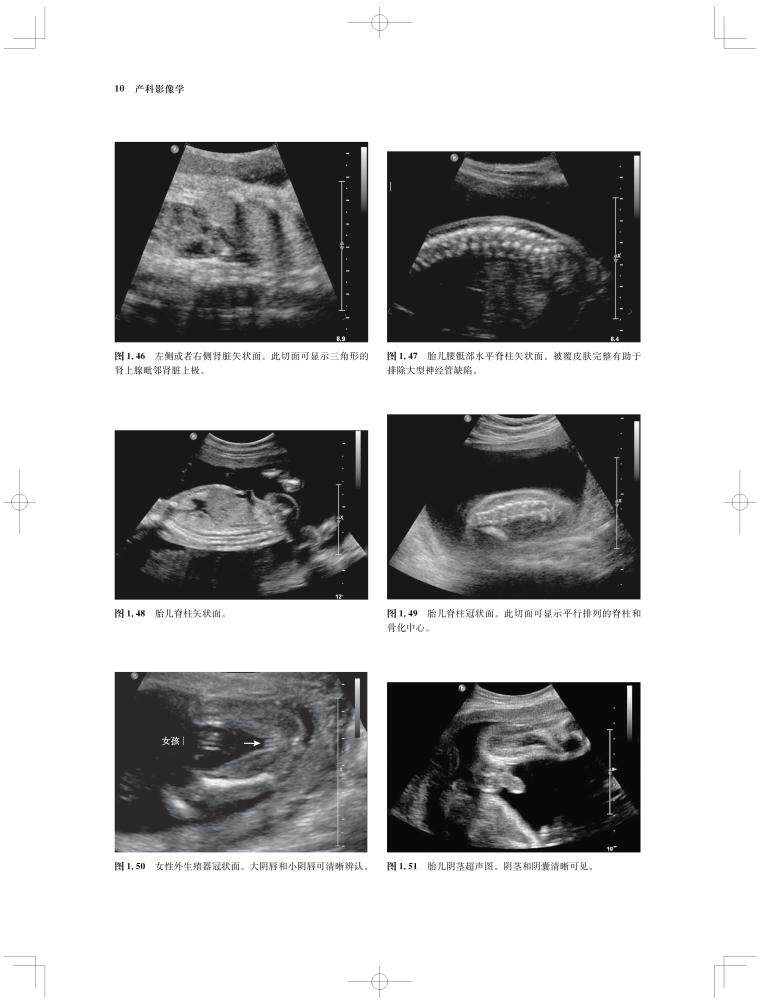

内容涵盖了胎儿宫内疾病的所有病种,从疾病的概述、流行病学、病因学、病理生理学,到临床表现、各类影像学技术的诊断和鉴别诊断,再到产前、产后的治疗和干预手段,都做了全面介绍,重点阐述了疾病的超声、X线、CT、MRI、PET、CT等影像学表现,以及诊断与鉴别诊断,并辅以大量标准化的影像学图片,图文并茂。

《产科影像学——胎儿诊断和监护》是Elsevier(Saunders)出版的“Expert Series”之一,由国际最顶尖的妇产科、生殖科、母胎医学和影像学专家共同编写,代表着该领域最顶尖的水平。书中配有大量典型影像图片,内容丰富全面,编写理念先进,侧重于疾病的影像学征象分析及鉴别诊断和诊断流程的制定,从临床思维上进行了更新;同时兼顾临床和病理医师,重点内容以列表、提要、要点的形式进行总结,提纲挈领,方便读者阅读、记忆。对于每天不断进行诊断与鉴别胎儿疾病的影像工作者、病理科和临床医师而言,具有重要的参考价值。